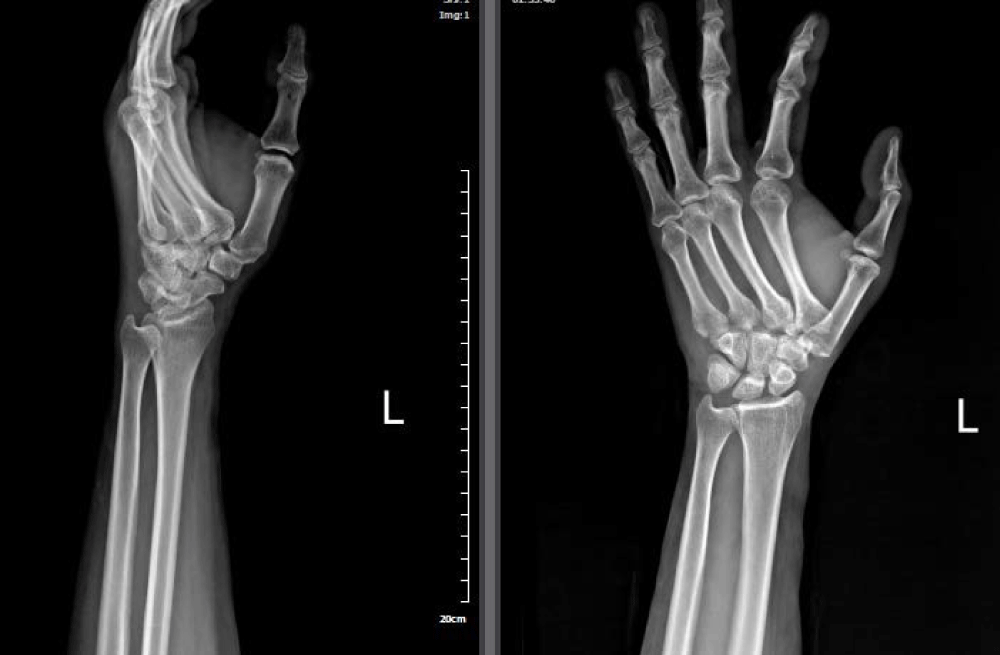

Here we presented a 46 year old female suffering the second and third CMC injury. She transferred to our emergency department with extreme annoying left hand pain and severe swelling after a car crash; she was not able to move her fingers. Neurovascular examination was unremarkable. Primary evaluation was conducted. X-ray of her left hand illustrated second and third CMC dislocation (Figure 1). Her hand was stabilized in volar splint and moved to operation room. Closed perceutanous pinning under fluoroscopy was conducted (Figure 2).

Figure 1: Initial x-ray study of a 46-year-old female illustrating 2nd, 3rd CMC dislocation.